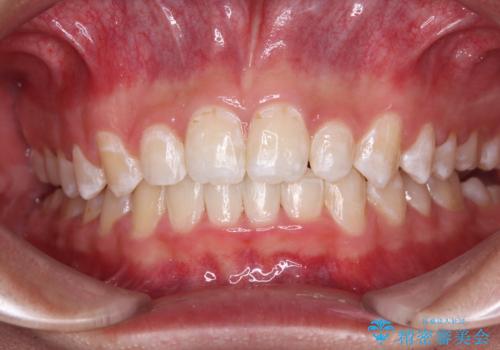

- 強い咬み合わせと前歯のデコボコを気にして来院された患者様です。

下顎前歯が全て隠れてしまうほどの深い咬合で、左右の奥歯は1歯対1歯で咬み合う状態でした。

前方に移動している上顎臼歯を補助装置にて遠心移動させることで1歯対2歯の臼歯咬合を目指し、同時に深い咬合を改善していくこととしました。

このような咬み合わせの場合、治療期間は2年以上がかかることが一般的で、3年程度かかることもありえるケースです。

強く深い咬み合わせにより下顎装置は頻繁に脱離するため、治療期間が長くなりますが、予定通りに終了させることができました。